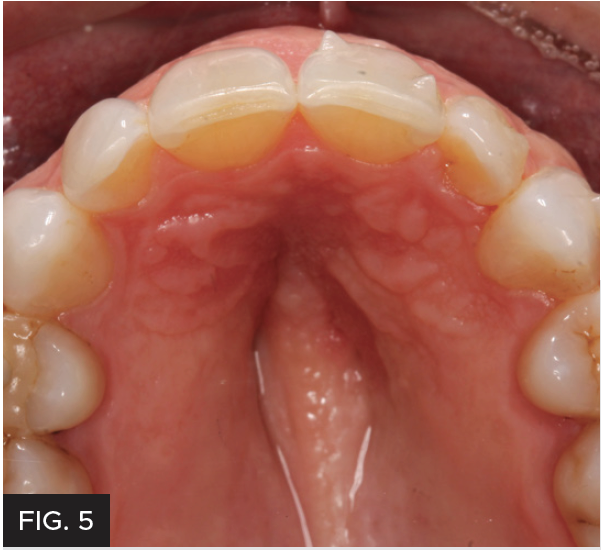

CLINICAL EXAMINATION AND FINDINGS

Examination and images, including the prescribed series of AACD photographs,2 revealed that #7 was normal, but smaller in crown size than ideal. Some tissue inflammation, likely related to orthodontic attachments, was visible on the tooth’s distal surface.The photographs and clinical data were reviewed with the patient. The main esthetic challenge would be to recreate incisal translucency and characteristics. (FIG 1 & 2)

Post-operative full smile view after orthodontic treatment completed and shows the completed composite restoration.